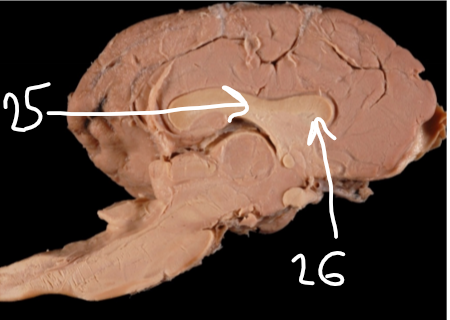

25

New cards

Septum pellucidum (separating lateral ventricles)

26

Septal nuclei